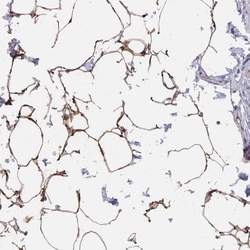

Invitrogen™ TUSC5 Polyclonal Antibody

| Applications | Immunohistochemistry (Paraffin) |